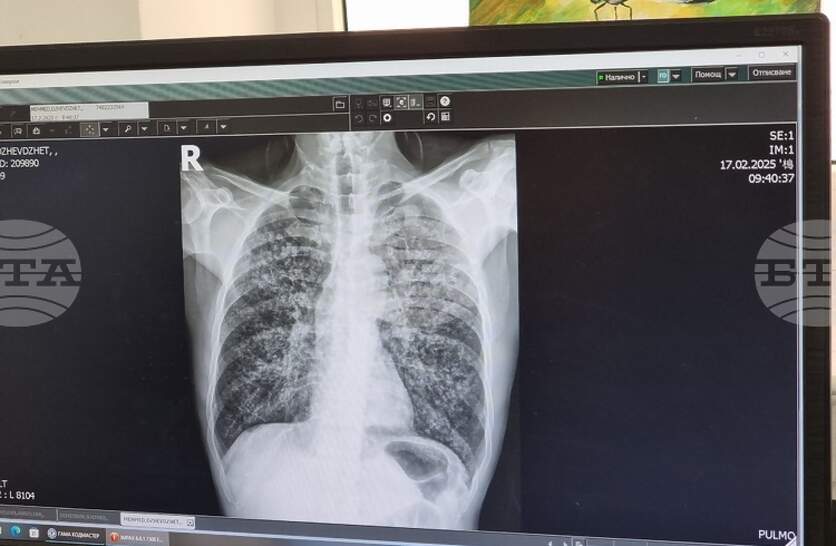

Безплатни прегледи и изследвания за туберкулоза ще се извършват в пневмо-фтизиатричното отделение на областната Многопрофилна болница за активно лечение (МБАЛ) „Свети Пантелеймон“ в Ямбол от 23-ти до 27 март, съобщиха от лечебното заведение. Скринингът ще се извършва от 12:00 ч. до 15:00 часа в петте дни. Седмицата на отворените врати е част от кампания на Министерството на здравеопазването. Тя се организира във връзка със Световния ден за борба с туберкулозата – 24 март, който тази година е под мотото „Да! Ние можем да спрем туберкулозата!“. През 2025 г. в област Ямбол са регистрирани 18 случая на туберкулозна инфекция, каза директорът на Регионалната здравна инспекция д-р Радостина Калчева. Туберкулозата засяга предимно хора с нисък социален и здравен статус, затова в кампанията активно се включват и ромски медиатори, каза д-р Калчева.